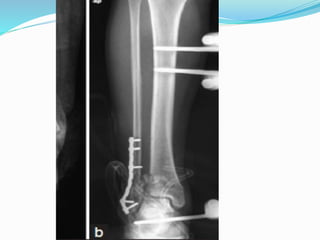

Types of surgical treatement

 1. ORIF, Open Reduction Internal ‘‘rigid’’ Fixation

 2 External Fixation with minimal osteosynthesis

 3 Closed Reduction Internal ‘‘biological’’ Fixation.

(MIPPO Technique)

 4. Intramedullary nailing

 5.Two stage protocol

TWO STAGE PROTOCAL

 All B3 and C type 0f

AO/OTA

 Ruedi & Allgower type 3

 1. Fix the # fibula(90%)

through postero lateral

approach to regain the

correct lengh of the tibia

and facilitate three

dimensional view of the

fracture

 2.External fixator-

a)Ankle Spanning -rigid

-articulated

b) Non spanning -

illizarov

-hydride

First step

Second stage

 After 10-14 days average(10

days)

 Remove the Ex Fix

 Through antero lateral

incision

 Articular reduction & fixation

with pre countered plate and

screws

 Additional antero medial

incision may require to fix

MM or large medial fragment

 Two incision required-

maintain not<6-7 cm

between two incision